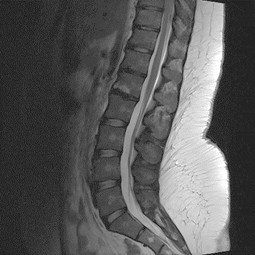

Degenerative Lumbalskoliose Wenn sich der bereits beschriebene Verschleiß in mehreren Wirbelelementen findet, kann es zu einer Verkrümmung der Wirbelsäule zur Seite hin (sog ‚Skoliose‘) kommen Normalerweise tritt eine Skoliose im Alter zwischen 10 und 12 auf. Die weitaus häufigsten degenerativen Beschwerden der Wirbelsäule finden sich im Lendenwirbelsäule (LWS) Bandscheibenvorfälle Bei Bandscheibenvorfällen (Abb 4a und 4b, MRT bei Bandscheibenvorfall LWK 3/4 rechts) wird zumeist über einen dorsalen Zugang eine mikrochirurgische Operation vorgenommen (Mikrodiscektomie). Im Laufe des Lebens kann es anlagebedingt, sowie durch allgemeinen Verschleiß zu Veränderungen der anatomischen Charakterzüge kommen, so dass die funktionellen Eigenschaften der Wirbelsäule beeinträchtigt werden Diese Veränderungen werden als degenerative Veränderungen bezeichnet.

Volkskrankheit Rückenschmerzen Der Verschleiß der Wirbelsäule, der auch als Degeneration bezeichnet wird, nimmt individuell unterschiedlich mit voranschreitendem Lebensalter zu Dies hängt einerseits von äußeren Faktoren ab, zum Beispiel jahrelanger schwerer körperlicher Tätigkeit, kann aber auch genetisch. Besonderheiten der Brustwirbelsäule Der Unterschied zu anderen Segmenten der Wirbelsäule (HWS und LWS) liegt in der speziellen AnatomieSo nimmt die Größe der Bandscheiben von oben nach unten zu Im Bereich der Halswirbelsäule sind die Bandscheiben ca 3 mm dick, in der Brustwirbelsäule 5 mm und in der Lendenwirbelsäule etwa 7 mm Der Wirbelkanal ist im Bereich der Brustwirbelsäule. Degenerative Veränderung lassen sich meist von inflammatorischen, traumatischen und neoplastischen Prozessen abgrenzen Problematisch ist weiterhin die oft fehlende Korrelation von Befunden im CT oder MRT und der klinischen Symptomatik, weswegen die klinische Symptomatik und die entsprechenden Kenntnisse vorliegen müssen.